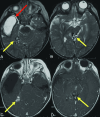

Background: Hereditary hemorrhagic telangiectasia is an autosomal dominant vascular dysplasia characterized by mucocutaneous telangiectasias, recurrent epistaxis, and organ vascular malformations including in the brain, which occur in about 10% of patients. These brain vascular malformations include high-flow AVMs and AVFs as well as low-flow capillary malformations. High-flow lesions can rupture, causing neurologic morbidity and mortality.

Analysis: In this article, a multidisciplinary group of experts on hereditary hemorrhagic telangiectasia reviewed data that support screening guidelines and counter arguments against screening. Children with hereditary hemorrhagic telangiectasia have a preponderance of high-flow lesions including AVFs, which have the highest rupture risk. The rupture risk among children is estimated at about 0.7% per lesion per year and is additive across lesions and during a lifetime. ARUBA, an adult clinical trial of expectant medical management versus treatment of unruptured brain AVMs, favored medical management at 5 years but is not applicable to pediatric patients with hereditary hemorrhagic telangiectasia given the life expectancy of a child. Additionally, interventional, radiosurgical, and surgical techniques have improved with time. Experienced neurovascular experts can prospectively determine the best treatment for each child on the basis of local resources. The "watch and wait" approach to imaging means that children with brain vascular malformations will not be identified until a potentially life-threatening and deficit-producing intracerebral hemorrhage occurs. This expert group does not deem this to be an acceptable trade-off.